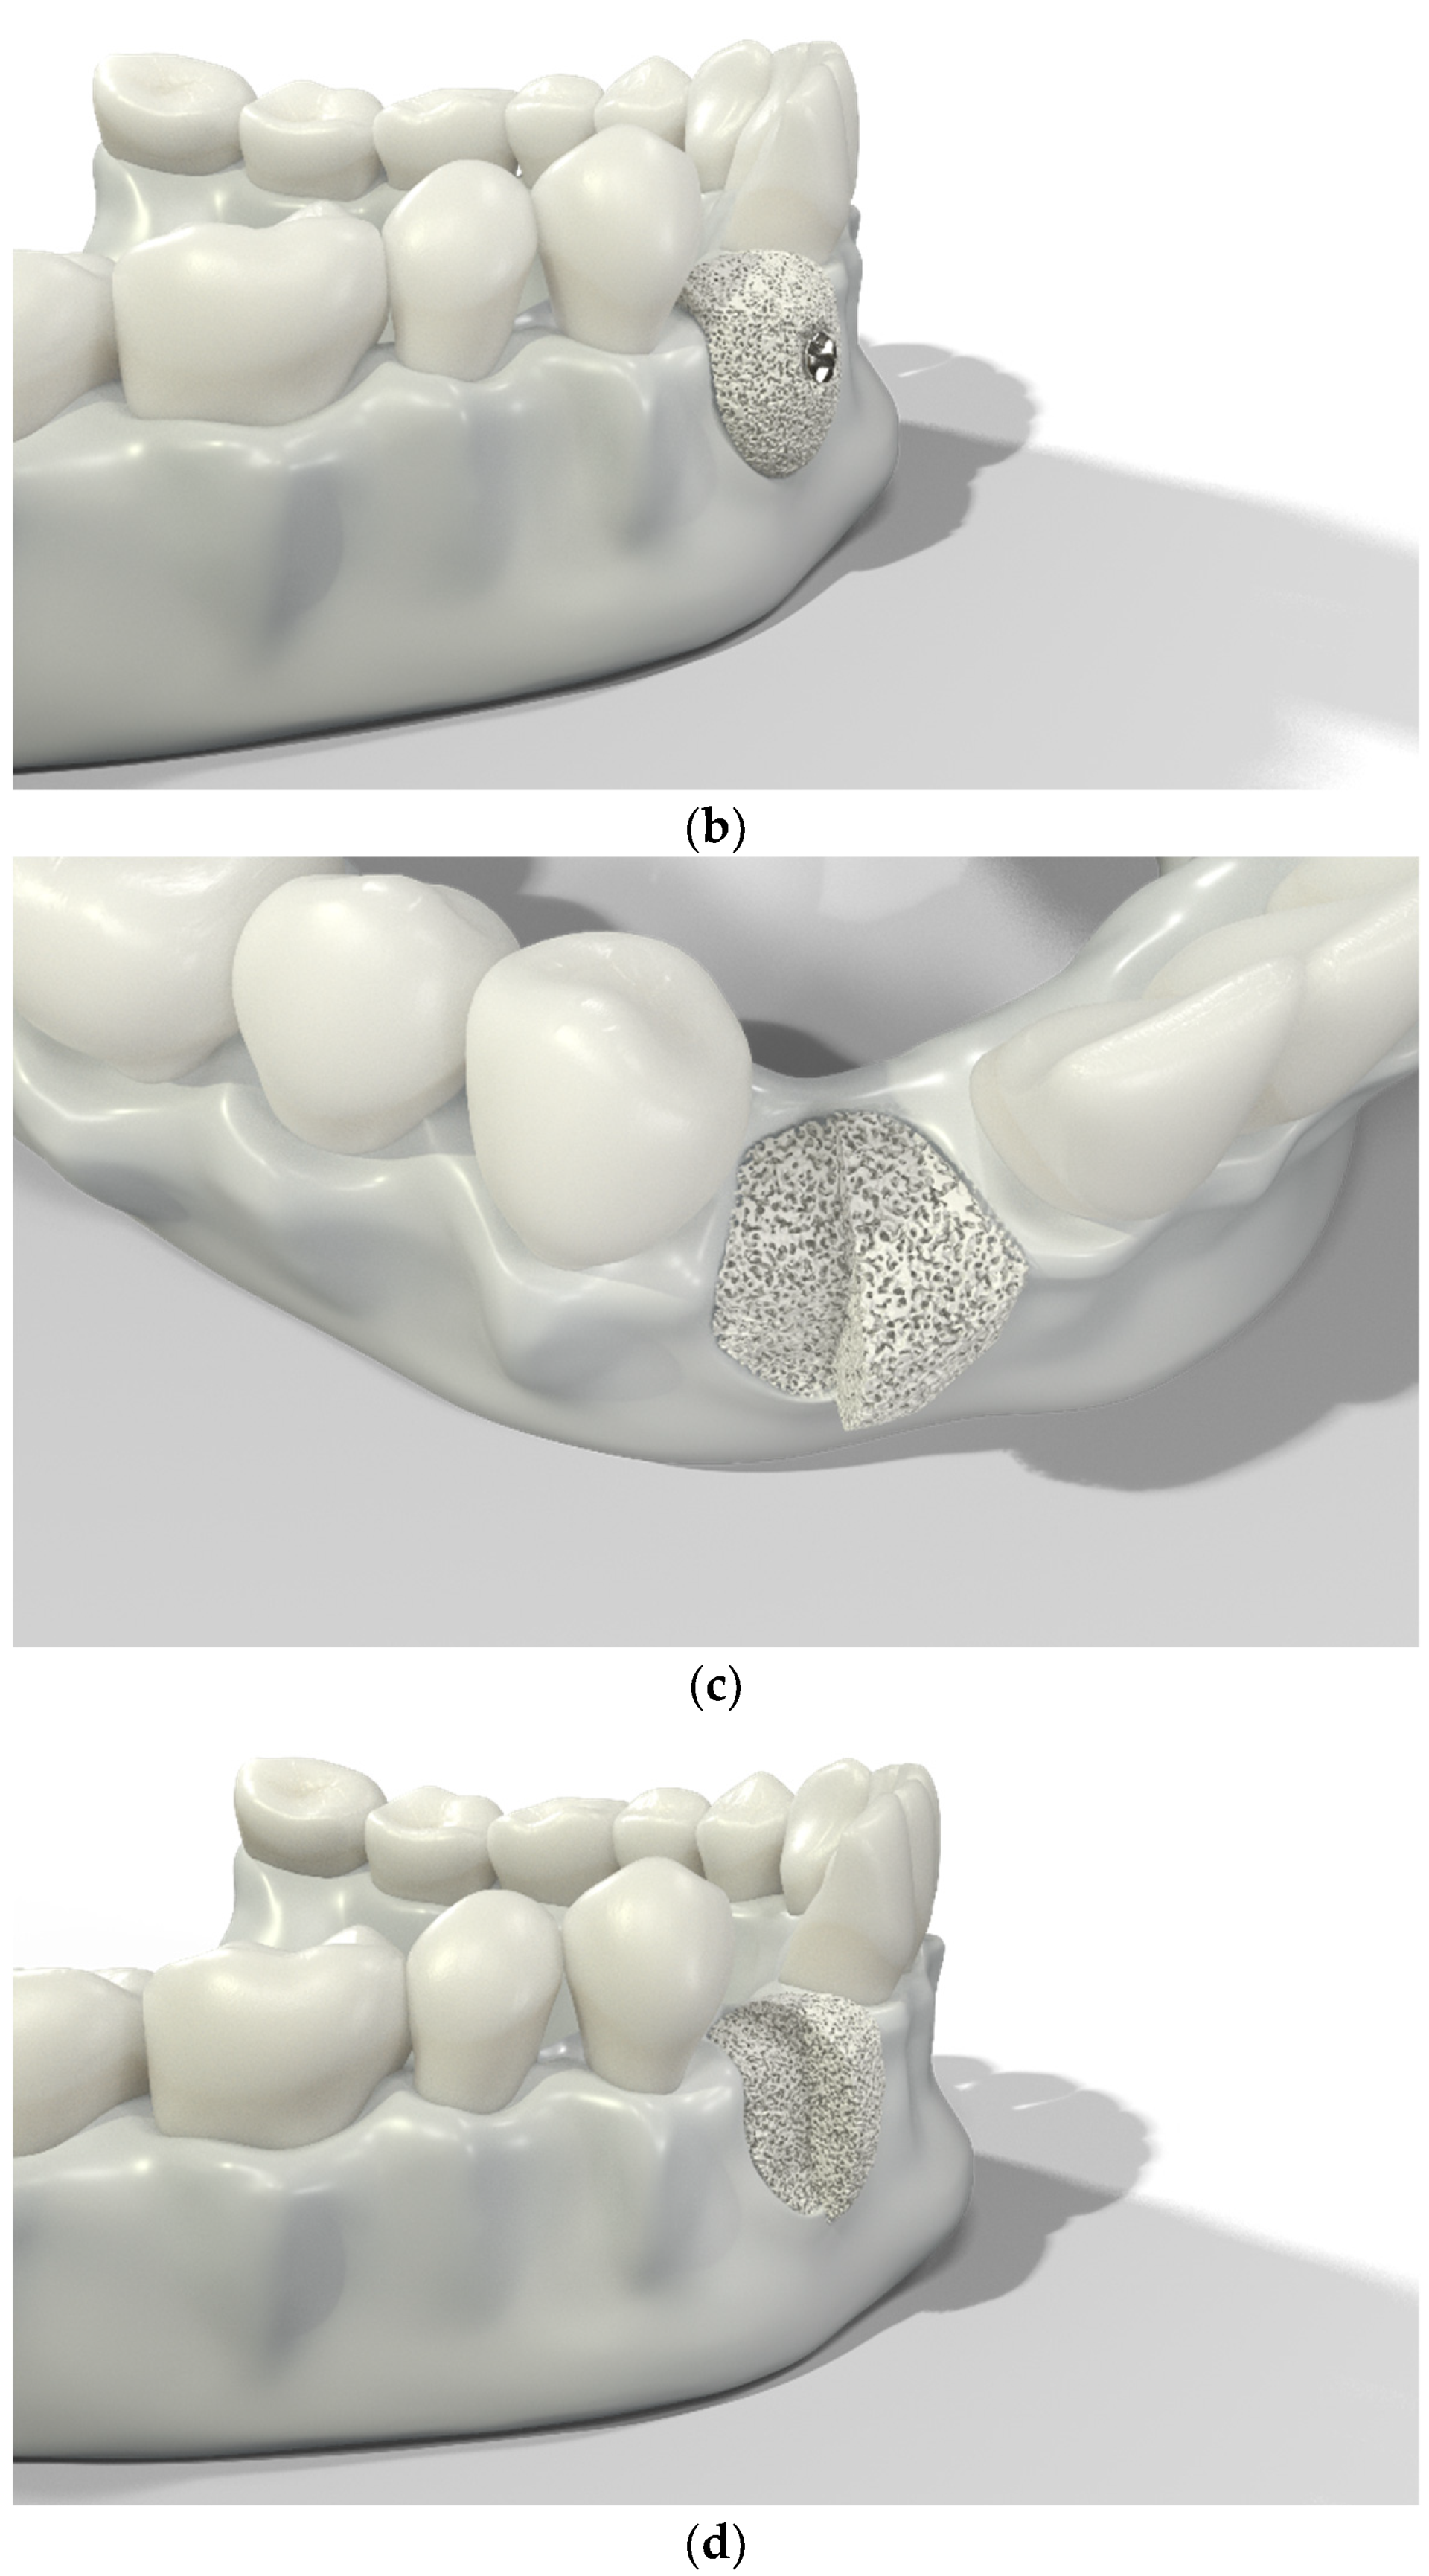

Over-contouring was defined as an over-augmentation of the alveolar process beyond the extent of the adjacent bone level (Figure 1). The reason for over-augmenting the alveolar process is often an anticipated shrinkage of the bone substitution material during the healing phase. Two patients were selected as examples to illustrate the term “over-contouring”. Patient 1 showed a Class III defect in the maxilla, and the alveolar ridge augmentation performed for correction was over-contoured (Figure 2). Patient 2 also showed a Class III defect in the maxilla, but the alveolar ridge augmentation performed for correction remained at the level of the surrounding bone (Figure 3).

Graphical 3D models to demonstrate surgical over-contouring during augmentation of the alveolar process. (a) Lateral view of the mandible with a single-tooth gap on the position of the second right incisor; the bone defect was compensated without exceeding the extent of the adjacent bone level. (b) Lateral view of the mandible with a single-tooth gap on the position of the second right incisor; the bone defect was over-compensated by an over-augmentation of the alveolar process beyond the extent of the adjacent bone level. This is defined here as “over-contouring”. (c) Isometric view of the mandible with a single-tooth gap on the position of the second right incisor; the difference between appropriate augmentation (left half) and over-contouring (right half) is clearly visible. (d) Lateral view of the mandible with a single-tooth gap on the position of the second right incisor; the difference between appropriate augmentation (left half) and over-contouring (right half) is easily recognizable.